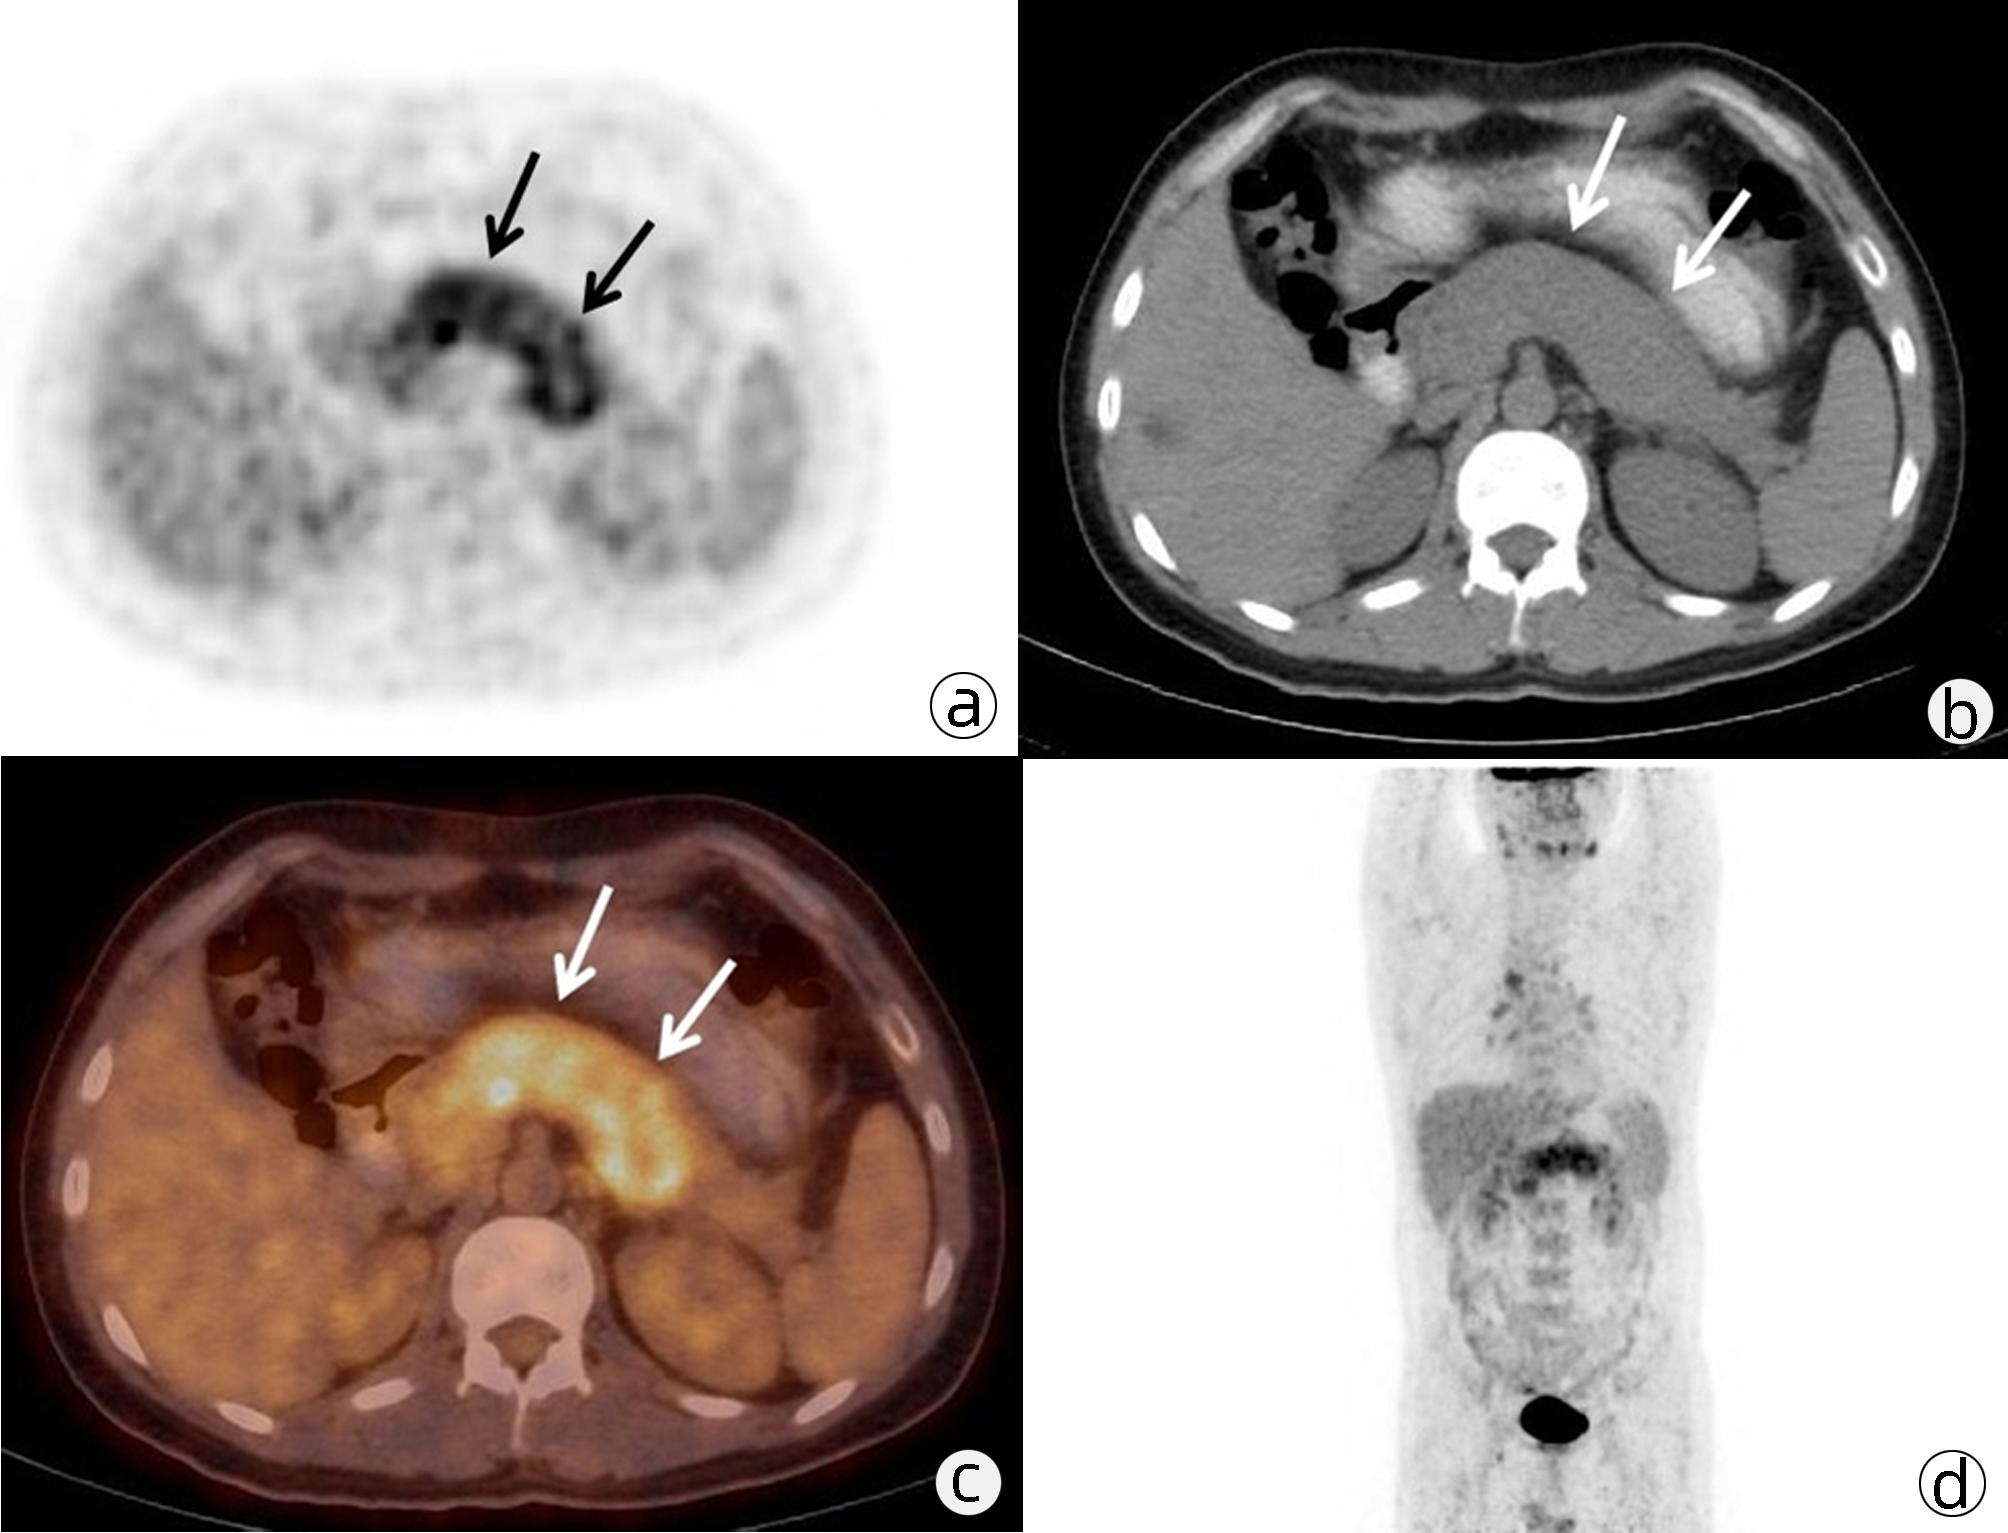

Value of 18F-FDG PET/CT, contrast-enhanced ultrasound, and their combined use in differential diagnosis of benign and malignant pancreatic lesions: A comparative study

Lichun ZHENG, Xiaoming ZHANG, Tianying YU, Jie LI, Xiaoqian DENG, Xiangliu OUYANG

2022, 38(12): 2774-2779. DOI: 10.3969/j.issn.1001-5256.2022.12.017

Abstract(2330) HTML (1630) PDF (3391KB)(64)

Objective  To assess the value of 18F-FDG PET/CT, contrast-enhanced ultrasound, and their combination in the differential diagnosis of benign and malignant pancreatic lesions.  Methods  A retrospective analysis was performed on patients with pancreatic lesions who underwent18F-FDG PET/CT and contrast-enhanced ultrasound who were admitted to Tangshan Gongren Hospital from January 2015 to December 2020. The imaging results were confirmed by pathology examination to evaluate diagnostic sensitivity, specificity, accuracy, positive and negative predictive value. The t-test was used for comparison of continuous data between two groups, and the chi-square test was used for comparison of categorical data between groups.  Results  There were 83 malignant lesions and 25 benign lesions in 108 patients. The sensitivity, specificity, accuracy, positive and negative predictive value were 86.75%, 80.00%, 85.19%, 93.51% and 64.52% for 18F-FDG PET/CT; and 69.88%, 76.00%, 71.30%, 90.63% and 43.18% for contrast-enhanced ultrasound, respectively. The two methods differed significantly in sensitivity and accuracy (all P < 0.05), but not in specificity, negative and positive predictive value (all P > 0.05). When combined with the contrast-enhanced ultrasound, 18F-FDG PET/CT had an increased sensitivity, specificity, accuracy, positive and negative predictive value of 90.36%, 84.00%, 88.89%, 94.94% and 72.41%, respectively, though this was not statistically significant due to the increased signal of blood supply in the lesions.  Conclusion  18F-FDG PET/CT has a better performance than contrast-enhanced ultrasound in the differential diagnosis of benign and malignant pancreatic lesions, and their combination can improve the diagnostic value.